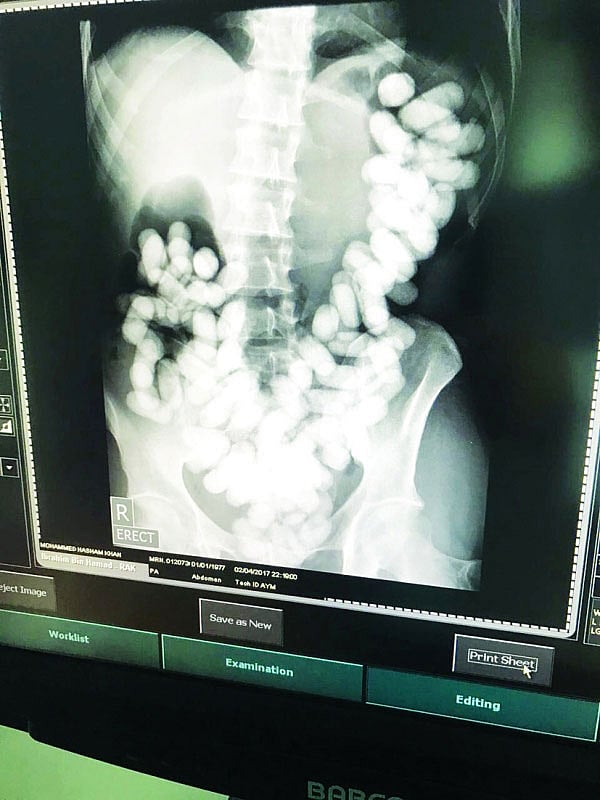

Dubai: An Asian man was arrested recently at Ras Al Khaimah International Airport for smuggling in 115 drug capsules concealed inside his stomach.

Officers from the airport’s department of drug control then carried out a thorough examination and discovered 115 narcotic capsules in the suspect’s bowels.